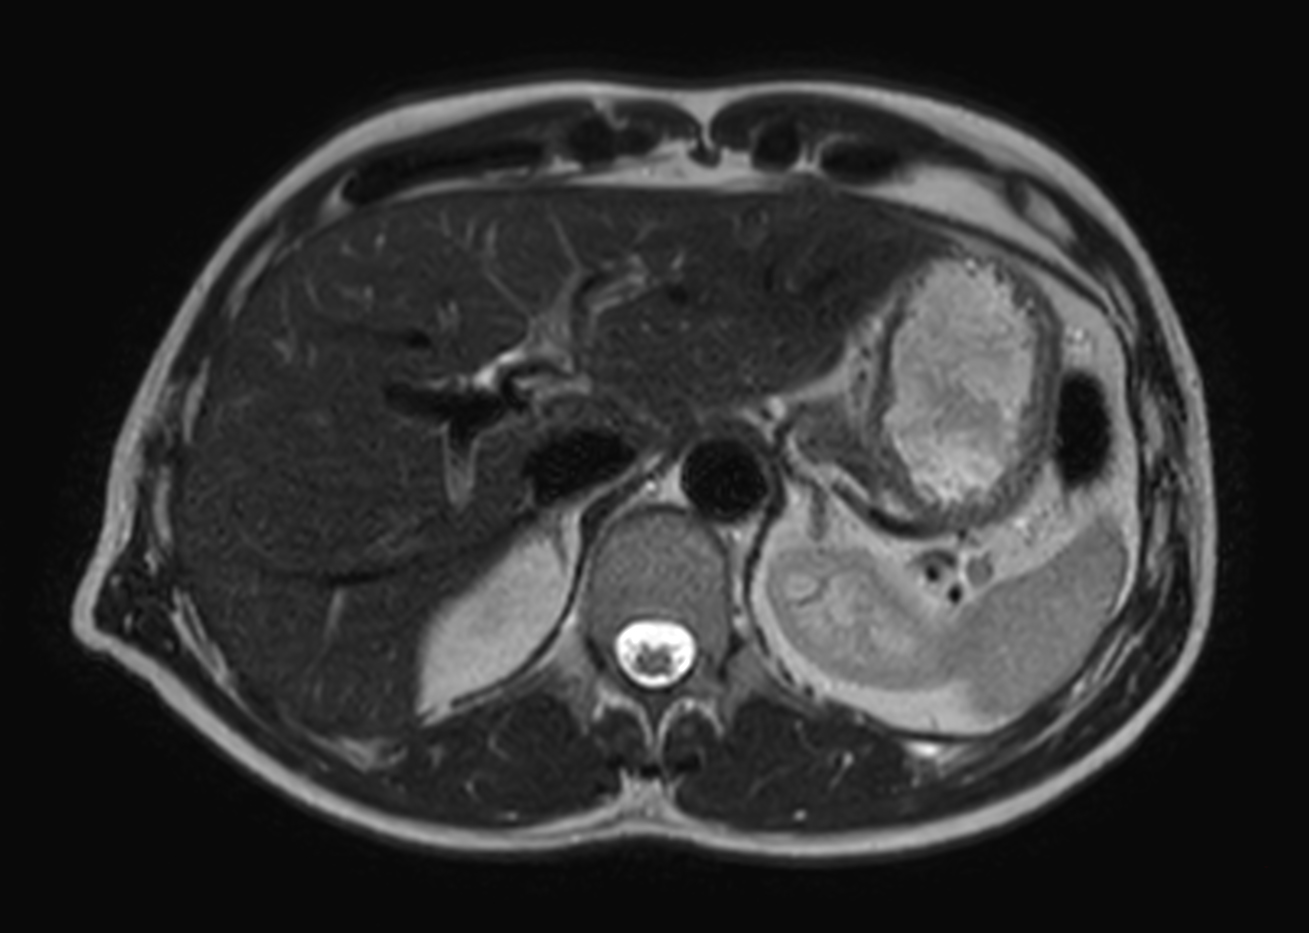

Helium-free MR operations:

Liver on BlueSeal magnet

Spital Uster, Switzerland

• Coil

• Clinical Application